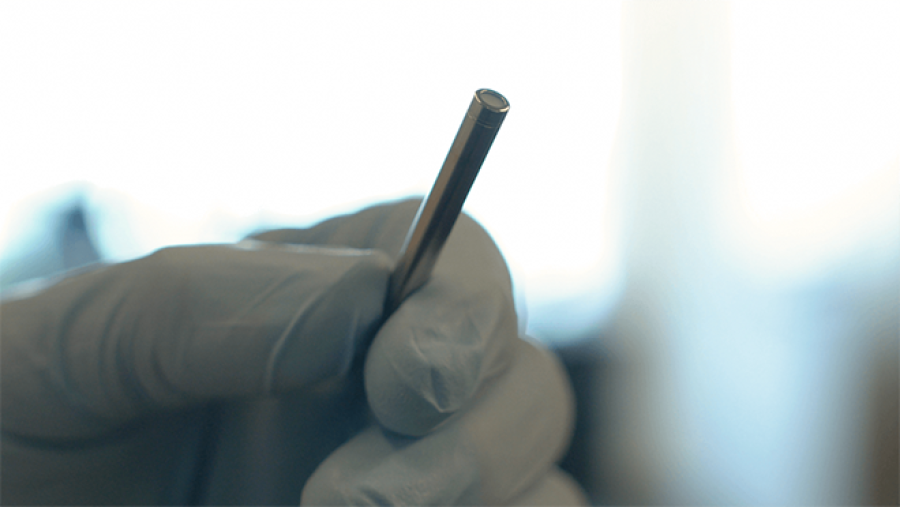

Researchers develop a new type of injectable electrode for neuromodulation therapy.